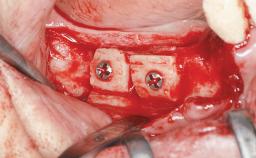

A 46-year-old woman was referred for treatment whose main complaints were mobility of her fixed partial dentures (right maxilla and left mandible) and periodontal bleeding during function. She also reported having taken systemic antibiotics to treat recurrent swelling in the area of the upper left molars. The patient had not seen a dentist for at least 2 years. She did not smoke and had no history of major systemic disease other than two minor orthopedic procedures some years back. The first-visit examination revealed poor plaque control, tooth mobility, periodontal disease, and a residual dentition widely associated with deep periodontal pockets.

| Bone Augmentation | Horizontal|Staged|Vertical |

| Augmentation Materials | Autogenous chips|Autogenous block(s)|Xenogenous |

| Bone Volume | Deficient vertically or deficient vertically AND horizontally |